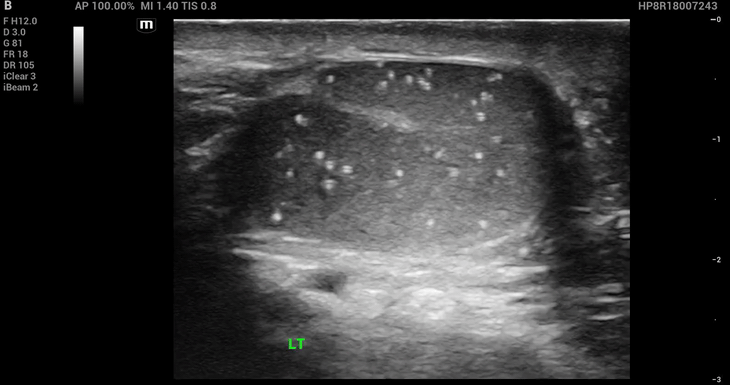

POCUS images of the left testicle:

Findings of bedside ultrasound:

• Multiple punctate, non-shadowing, uniformly sized, hyperechoic foci measuring 1–2 mm within the left testis.

• No testicular mass noted. No anechoic fluid collection around the left testis concerning for hydrocele. No other significant findings.

Diagnosis/Finding: Left testicular microlithiasis.